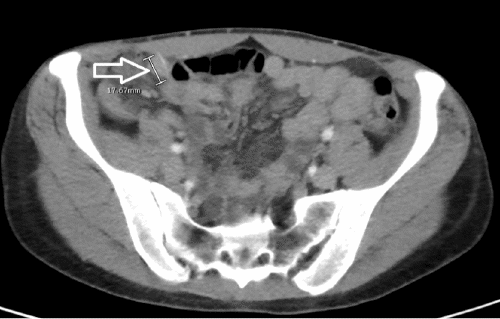

A 47-year-old female presented to the emergency department with a three-day history of waxing and waning right lower quadrant abdominal pain after eating a hamburger cooked on a home grill. She was afebrile, hemodynamically stable, with a white blood cell count of 5400 cells/ml. The patient had no evidence of peritonitis or free air, and a perforation was not suspected. CT imaging of the abdomen and pelvis demonstrated a metallic foreign body in the terminal ileum, without abscess or free air to suggest perforation (Figure 1).

Figure 1. CT Scan of Abdomen and Pelvis Depicting Metallic Foreign Body. Published with Permission

A) Terminal ileum, axial view

B) coronal view